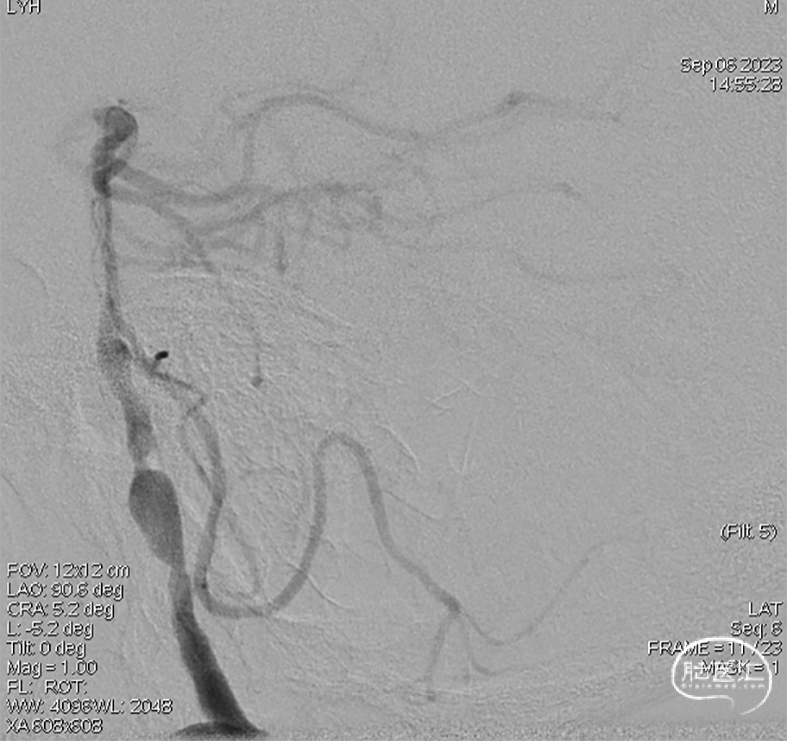

术后即刻DSA。

术后即刻稀释造影:“拉直”可见支架贴壁良好。